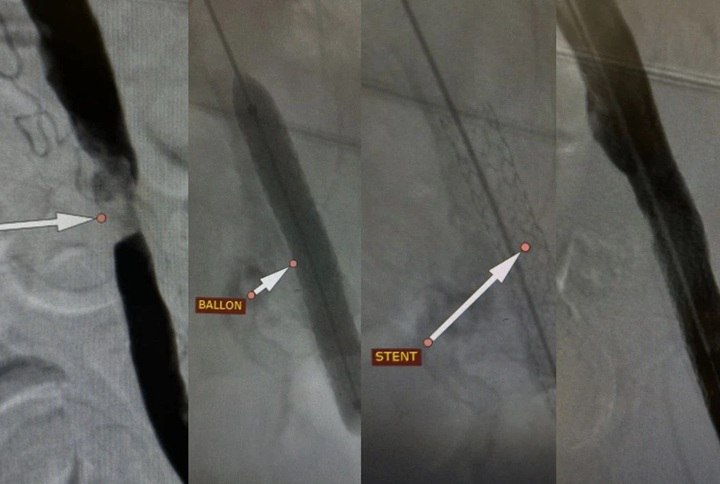

Но наши хирурги не сдались. Они провели уникальную высокотехнологичную операцию: через один крошечный прокол, без разрезов, установили в суженную артерию специальный стент. Он, как каркас, восстановил просвет сосуда и вернул в ногу жизнь. Самое невероятное — уже через сутки пациент встал и пошел.